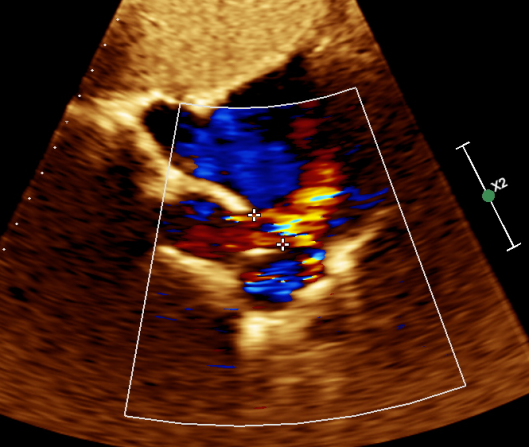

图 3 剑下双房切面显示房间隔回声失落约 17mm ,上腔静脉端无边,距下腔静脉约 30mm

图 4 CDFI 显示房水平可见左向右分流

图 5 右上肺静脉进入上腔静脉-右房入口处